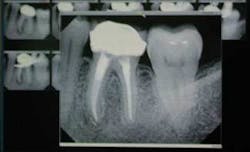

Beyond its importance as a time-saver in trauma cases, digital radiography is very helpful in the operating room. Instead of waiting for X-rays to be developed, we can begin the dentistry right away. This saves the patient from being under general anesthesia any longer than necessary. Also, if you want to check an implant or extraction site or endodontic procedure, you have the benefit of viewing the radiograph immediately. Take your digital X-ray sensor and laptop computer into the operating room. You can store your images and transfer them onto your office computer’s hard drive when you return to the office (Figure 5).